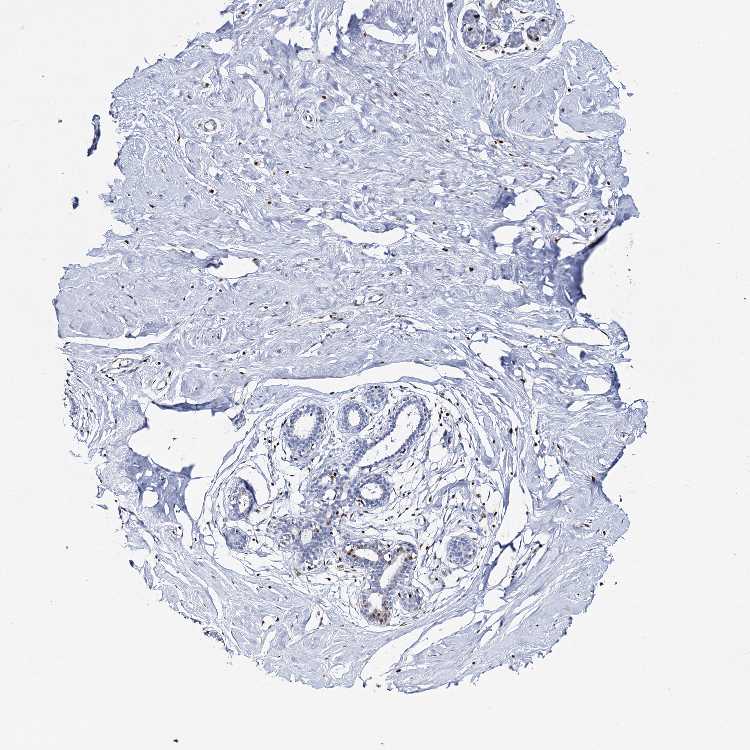

BREAST - Antibody stainingi

Antibody staining in the annotated cell types in the current human tissue is reported as not detected, low, medium, or high, based on conventional immunohistochemistry profiling in selected tissues. This score is based on the combination of the staining intensity and fraction of stained cells.

Each image is clickable and will lead to virtual microscopy that enables deeper exploration of all samples and also displays staining intensity scores, fraction scores and subcellular localization as well as patient and tissue information for each sample.

Antibody HPA035813Antibody CAB016395

Adipocytes Not detectedNot detected

Glandular cells LowNot detected

Myoepithelial cells Not detectedNot detected